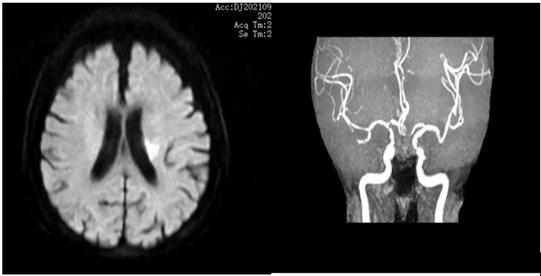

图11 左侧基底节区急性脑梗死,左侧MCA无明显狭窄,考虑为穿支动脉病变(图源 作者提供)

只要是与临床症状吻合的发生在穿支动脉区的急性孤立梗死灶,不考虑梗死灶大小,载体动脉无粥样硬化斑块或任何程度狭窄。